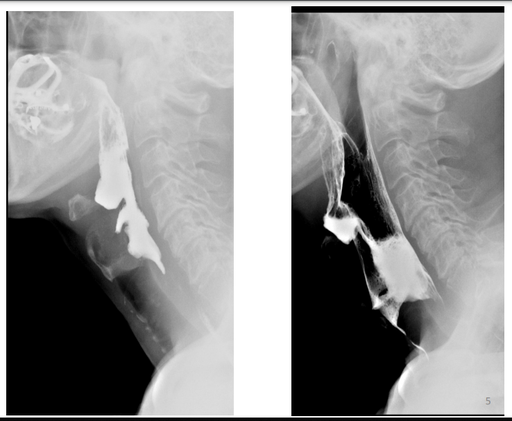

Contraste digestif en radiologie adulte

DANSE E. - UCL

Digestif MASTER 1